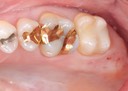

Joe Cha #18 pre-op

Joe Cha #18 composite removal

Joe Cha #18 prep

Alan Chinn #2 pre-op

Alan Chinn #2 amalgam removal

Alan Chinn #2 prep

Kyle Chock #30 pre-op

Kyle Chock #30 amalgam removal

Kyle Chock #30 prep

Mark Chun #2 pre-op

Mark Chun #2 prep

Mark Chun #2 prep buccal view

Frank Fukuda #15 pre-op

Frank Fukuda #15 lingual view

Frank Fukuda #15 prep

Scott Kanamori #18 pre-op

Scott Kanamori #18 prep

Scott Kanamori #18 finish

Ted Kanamori #14 pre-op

Ted Kanamori #14 amalgam removal

Ted Kanamori #14 prep

Brian Sato #4 pre-op

Brian Sato #4 caries removal

Brian Sato #4 prep

Mendel Sato #5 pre-op

Mendel Sato #5 prep

Gary Umeda #31 pre-op

Gary Umeda #31 caries removal

Gary Umeda #31 prep

Chris Woo #12 pre-op

Chris Woo #5 amalgam removal

Chris Woo #12 prep